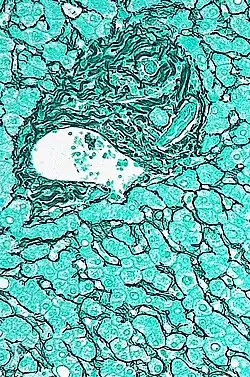

En histología del hígado, los espacios porta son estructuras tubulares tridimensionales, de tejido conjuntivo fibroso, situados en la periferia de los lobulillos hepáticos. Se originan en el hilio del hígado y se distribuyen en el interior de este órgano, siguiendo un patrón de ramificación sucesivo. Cada uno de los espacios porta contiene una tríada porta, integrada por: una arteriola rama de la arteria hepática, una rama de la vena porta hepática, un conductillo biliar.[1][2]

Si consideramos el lobulillo hepático tridimensional, que posee forma de prisma hexagonal, como la unidad funcional del hígado, los espacios porta se ubican en las seis aristas de la periferia.[3]

En su espesor llevan las ramificaciones de: la arteria hepática, de la vena porta, del conducto biliar, de vasos linfáticos y de fibras nerviosas.[1]